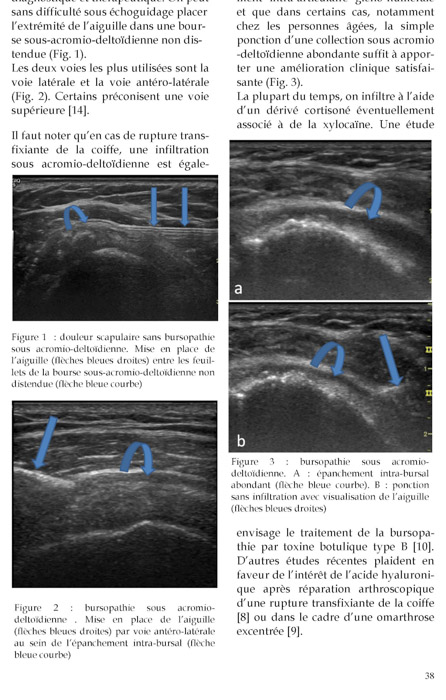

Gel Contact N°21

JUIN 2012